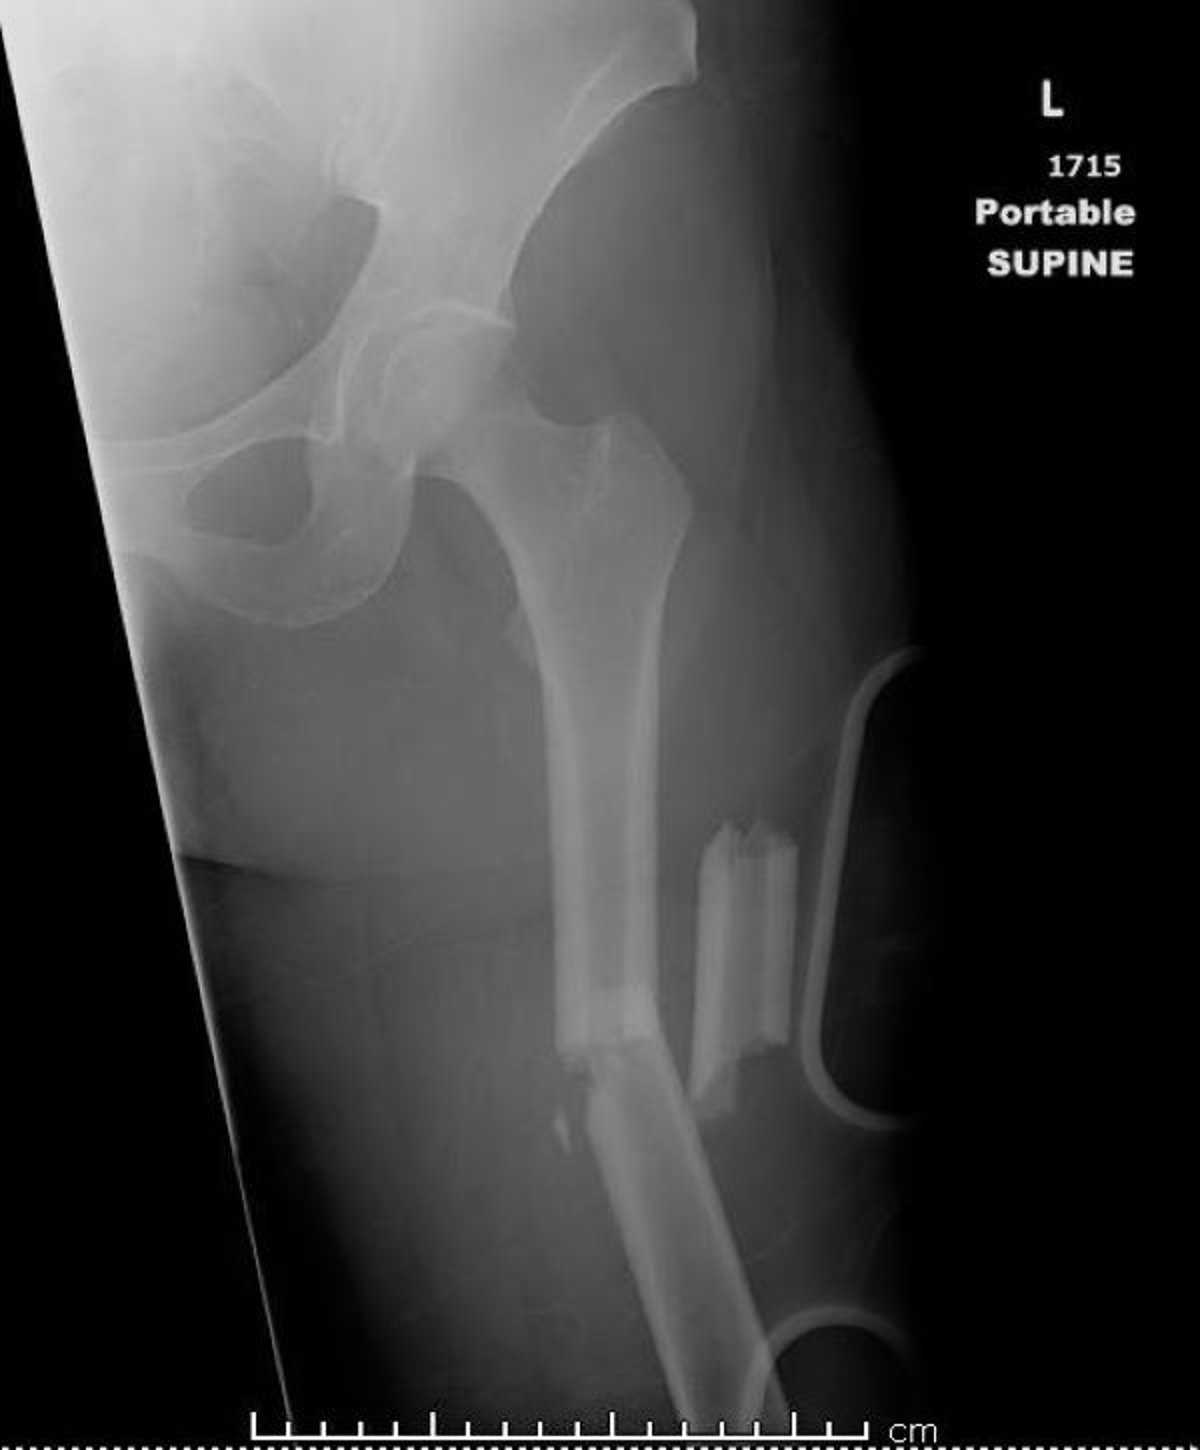

الكسر في منتصف عظم الفخذ

تُظهر هذه الصورة عظم الفخذ مكسورًا في أكثر من مكانين (كسر متفتت).

جرى استخدام الصورة بعد موافقة أصحابها Danielle Campagne, MD.